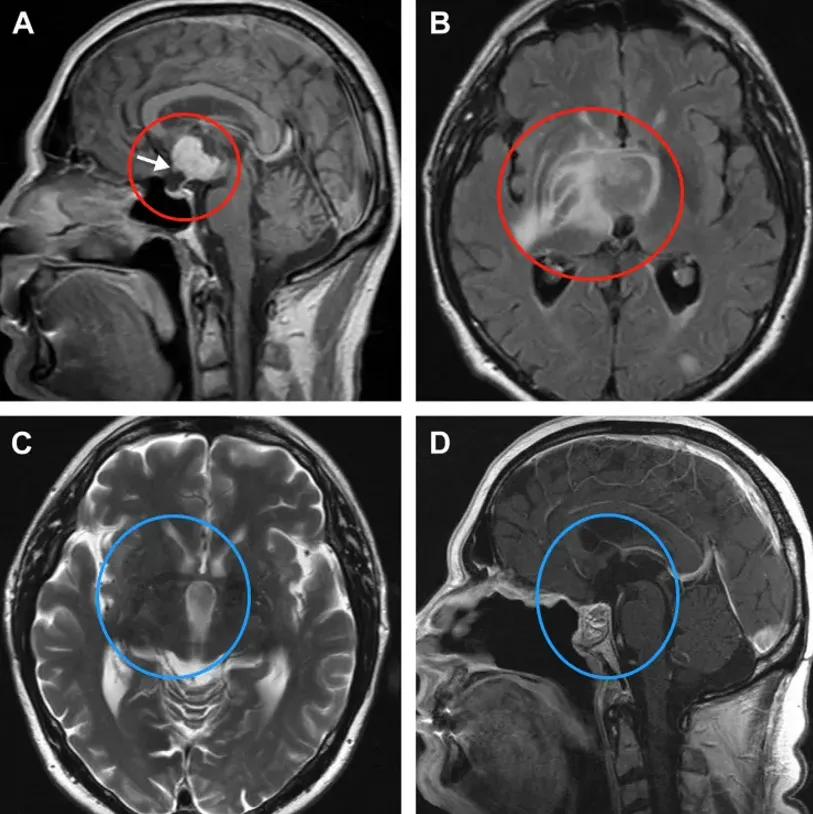

图1.A-B术前:鞍上增强MRI显示,肿瘤延伸至第三脑室,有实性成分(a)。视交叉受压,向前移位(箭头)。垂体和蝶鞍似乎正常。B:由于病灶周围水肿和反转恢复图像液体衰减并右侧基底神经节外侧延伸,怀疑下丘脑侵犯。施罗德教授在内镜下行全切术。C-D术后:术后2年MRI未见肿瘤复发,水肿完全消退,显示鼻中隔皮瓣重建颅底修复良好。